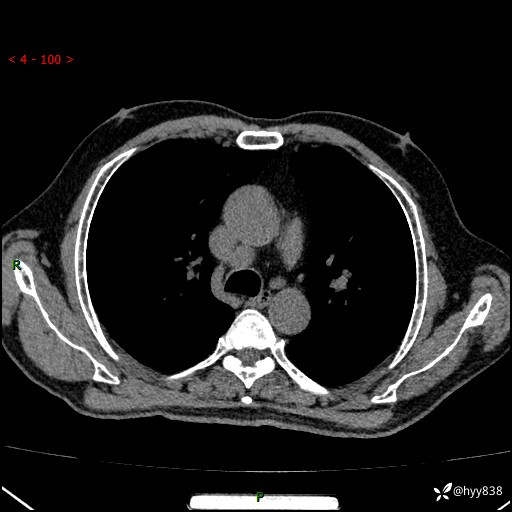

增强